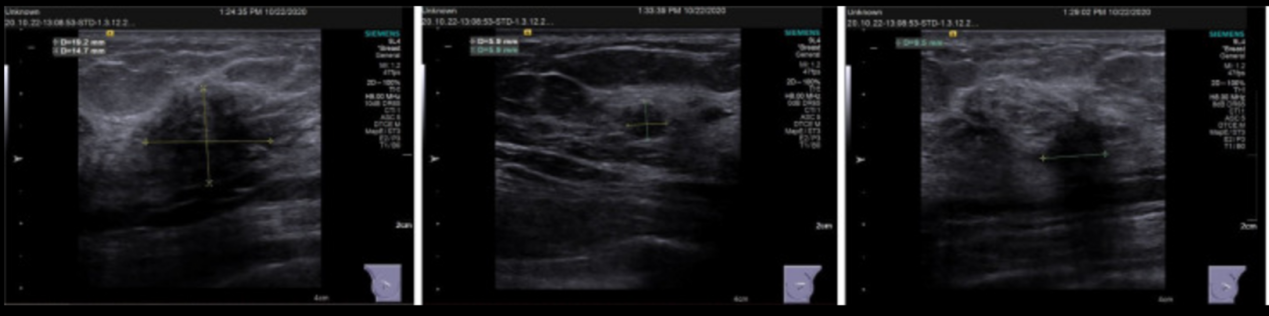

体格检查显示乳房对称,无桔皮外观改变,无酒窝,双乳头无回缩或凸出。在右乳1点钟位置可触及一肿块(大小2cm× 2cm),无压痛,边界不清,形状不规则,活动性差,皮肤粘连(-)。在左乳12点和1点位置,肿块(约0.5 cm× 0.5cm和1.5cm× 2cm)边界不清,形态不规则,活动性差,皮肤粘连(-)。锁骨上、锁骨下及双侧腋下未见肿大淋巴结(图1)。

图1

乳腺超声表现为:(1)双侧乳房上外侧象限实性占位(BI-rads4c);(2)左乳12点位置的实性肿块(BI-RADS 4B)。双侧腋下及左锁骨上区淋巴结。右锁骨未见肿大淋巴结(图1)(图2)。乳腺增强磁共振成像(MRI)表现为:右乳上内象限不规则增强(BI-rads4c);左乳上外侧象限斑片状异常信号(BI-rads4b);两个乳房的纤维囊性改变(BI-RADS 2)(图3)。

图2